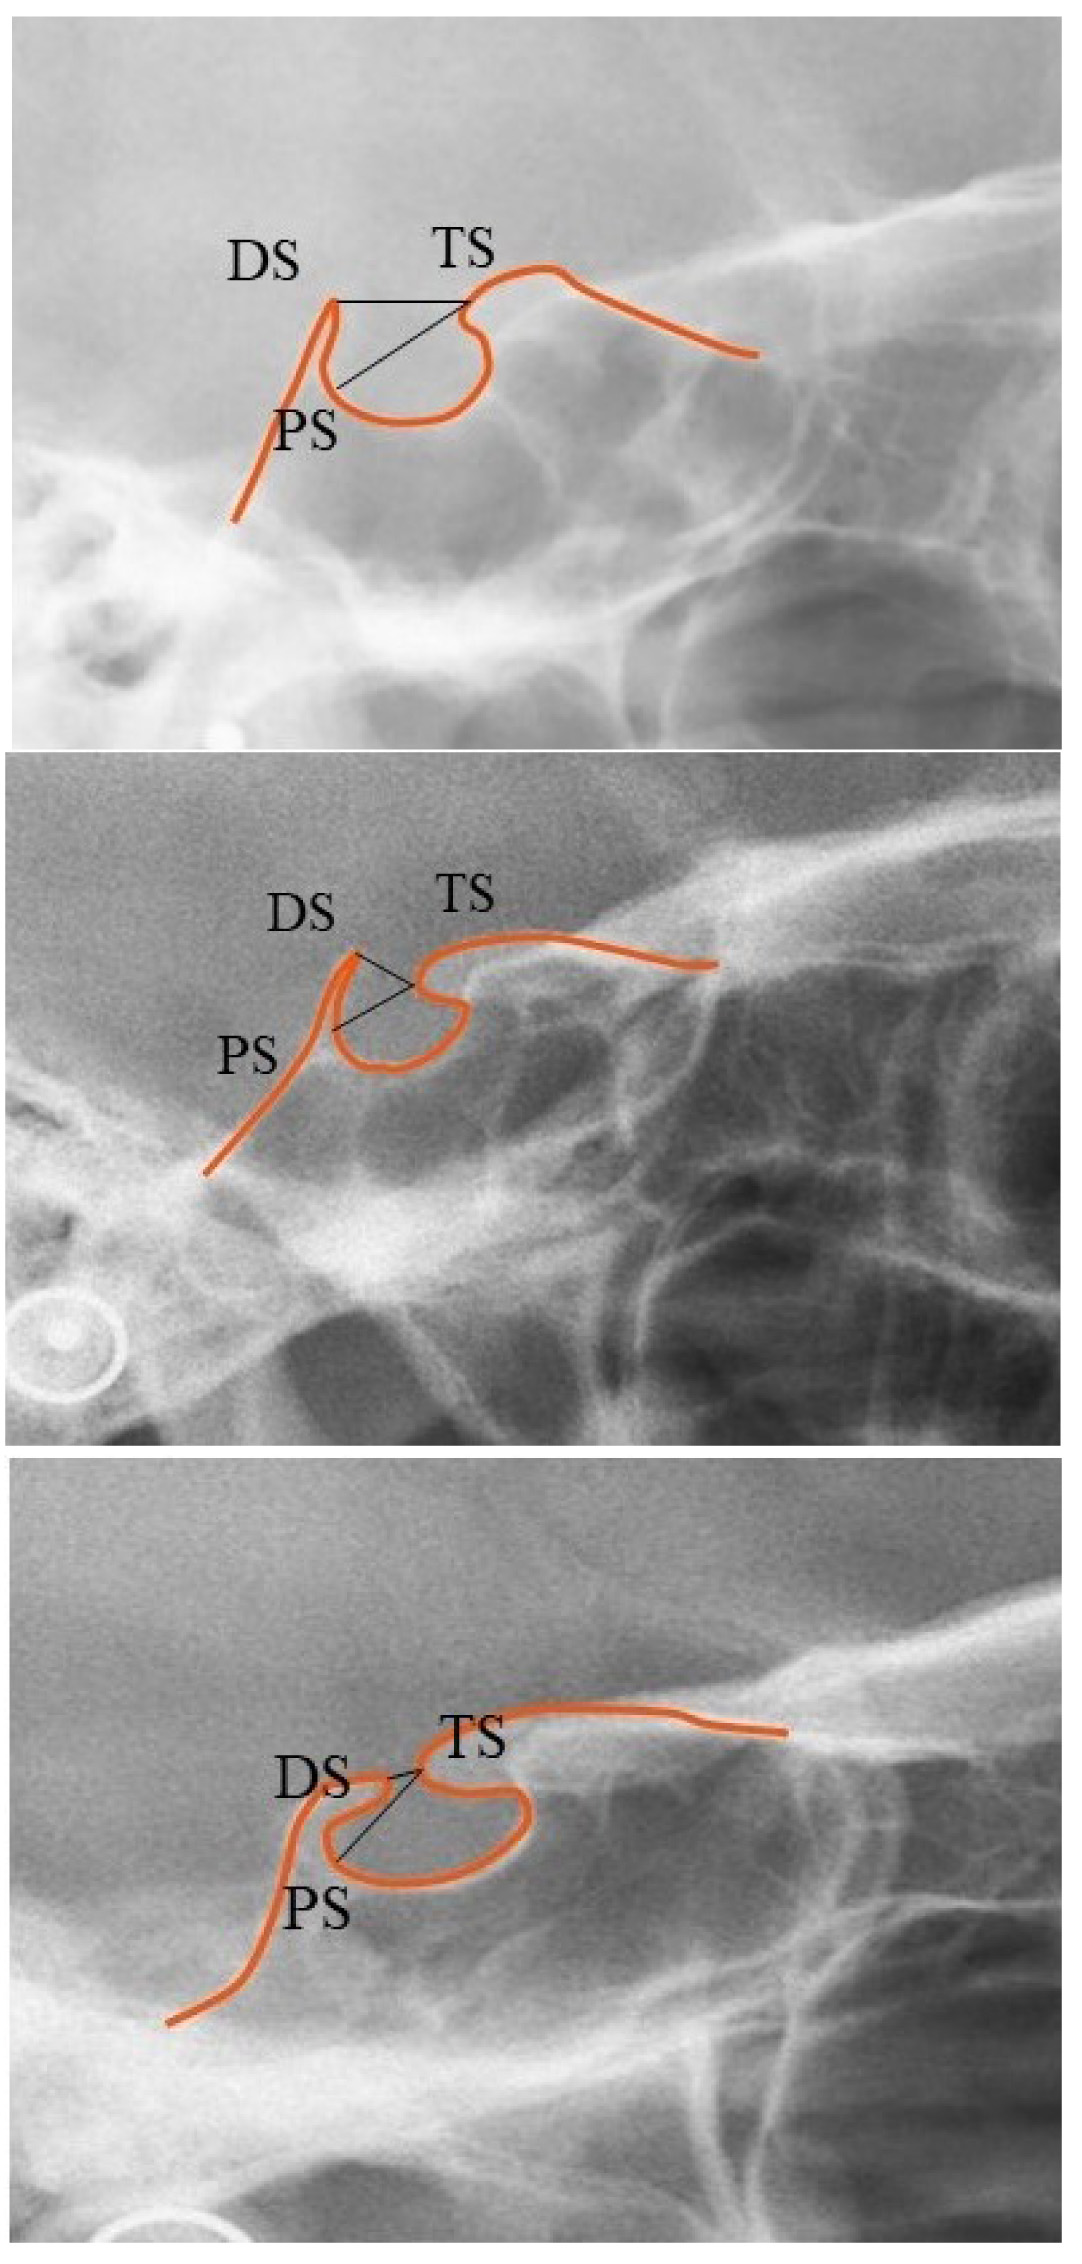

The extent of the STB on lateral cephalograms was assessed based on a standardized scoring scale as mentioned below [9]:

(1) Type I (no calcification of ICL): Length of the ST was greater than or equal to three-fourths of the A-P diameter (Fig. 2a) Type I sella turcica bridging.

(2) Type II (ICL partially calcified): Length of the ST was lesser than or equal to three-fourths of the A-P diameter (Fig. 2b) Type II sella turcica bridging.

(3) Type III (ICL ligament completely calcified): Diaphragma sella was radiographically visible (Fig. 2c) Type III sella turcica bridging.